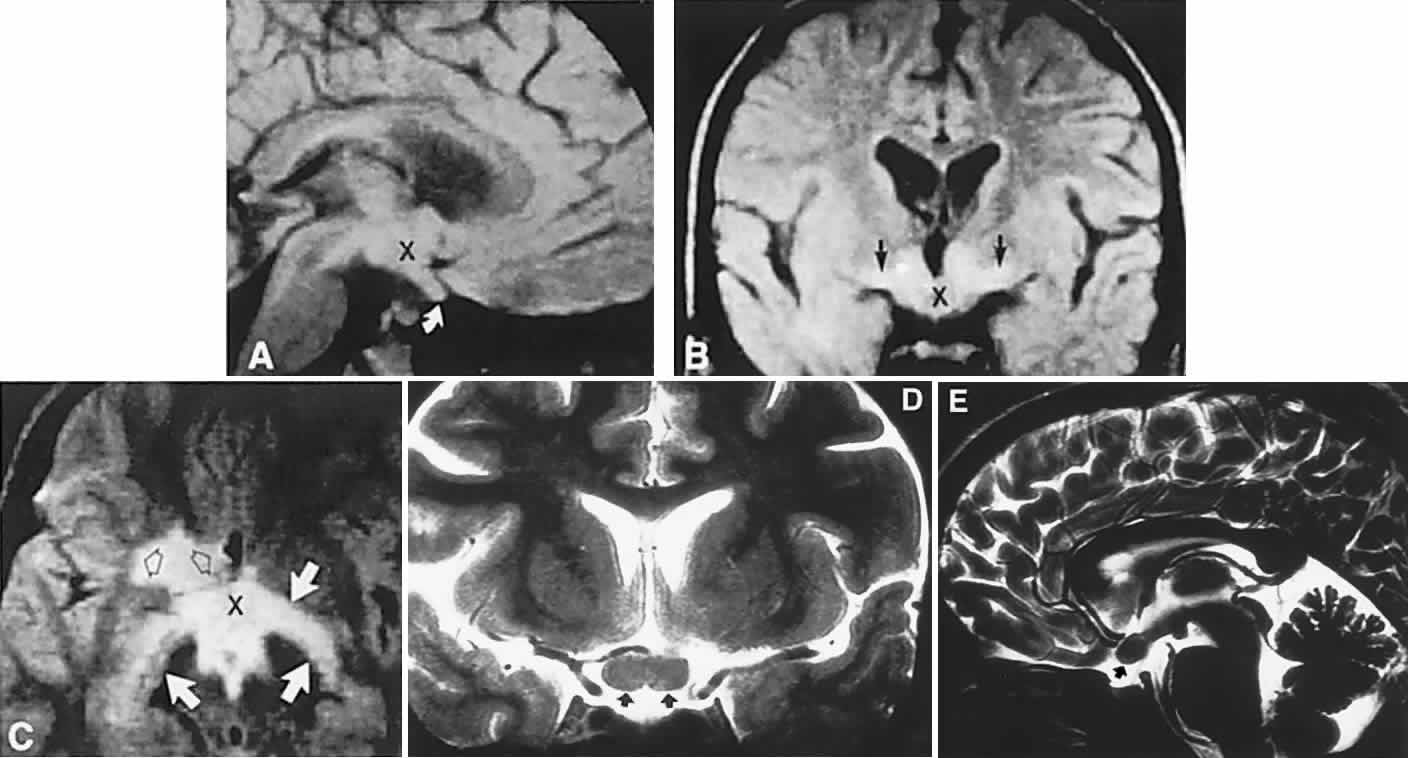

Fig. 2. Large prolactinoma. Original vision in the right eye (RE) was 8/200, left eye (LE) 1/200, with serum prolactin of 26,000 ng/ml and galactorrhea. Four months of bromocriptine reduced prolactin to 661 ng/ml, vision improved to RE 20/40, LE 20/50. At 3 years, vision was as follows: RE 20/30, LE 20/20; prolactin was 25.9 ng/ml. Enhanced magnetic resonance imaging. Sagittal (A) and coronal (C) images at diagnosis. Sagittal (B) and coronal (D) images at 2-year follow-up, showing dramatic shrinkage of the mass.